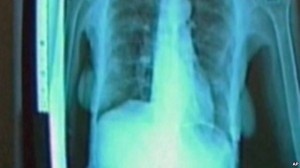

Shkarkimi i naftës shkakton kancerin